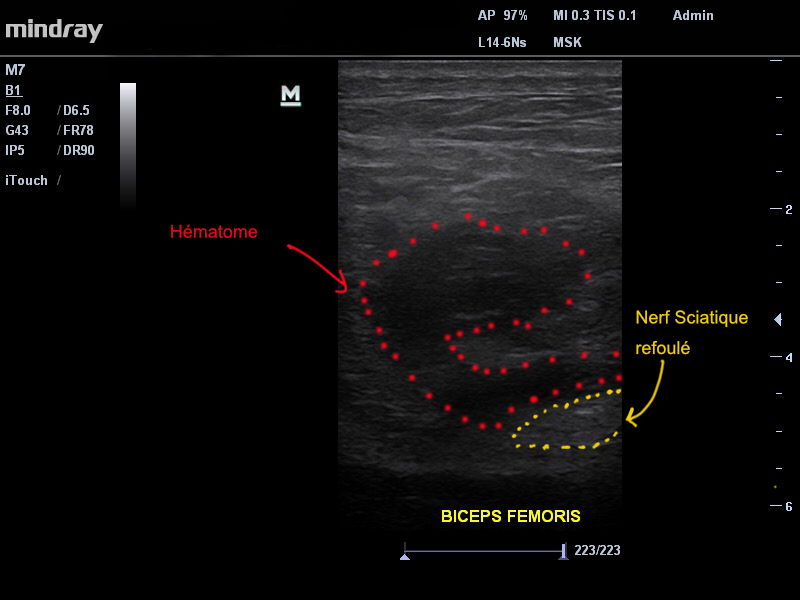

Notre examen retrouve la présence d’une déchirure musculaire de grade 3 ( sur une échelle de 0 à 4 ) au niveau de la portion la plus haute du biceps femoris (fait partie des muscles ischio-jambiers) à sa jonction avec le tendon conjoint. Fait important dans ce cas, l’hématome « refoule » latéralement le nerf sciatique réalisant à minima une irritation voire une compression de ce dernier. C’est la proximité de l’hématome avec ce nerf qui permet d’expliquer la douleur ressentie dans le mollet de notre patient. (Image 1).

Image 1. On retrouve à l’echographie un hématome important (points rouges) refoulant le nerf sciatique (points jaunes)

Certains hématomes peuvent évoluer vers une forme caillotée voir calcifiée . Dans ce cas, le risque est alors que cet hématome réalise une compression constante du nerf sciatique, pouvant nécessiter une intervention chirurgicale.